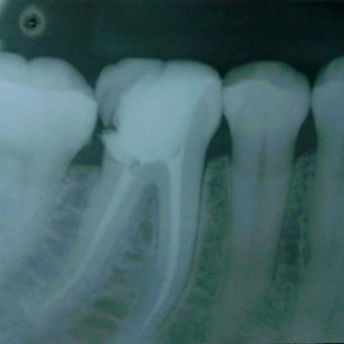

TRATAMENTO E RETRATAMENTO ENDODÔNTICO

DESOBTURAÇÃO

SELAMENTO PERFURAÇÕES

REMOÇÃO DE TRABALHO PROTÉTICO

CAPEAMENTO PULPAR

CIMENTAÇÃO DE

PINO DE FIBRA